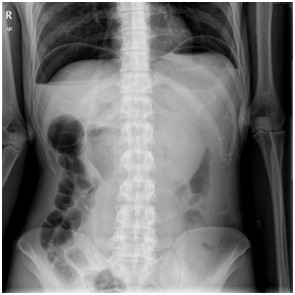

临床实践技能影像诊断模拟试题:某急腹症患者,其腹平片提示